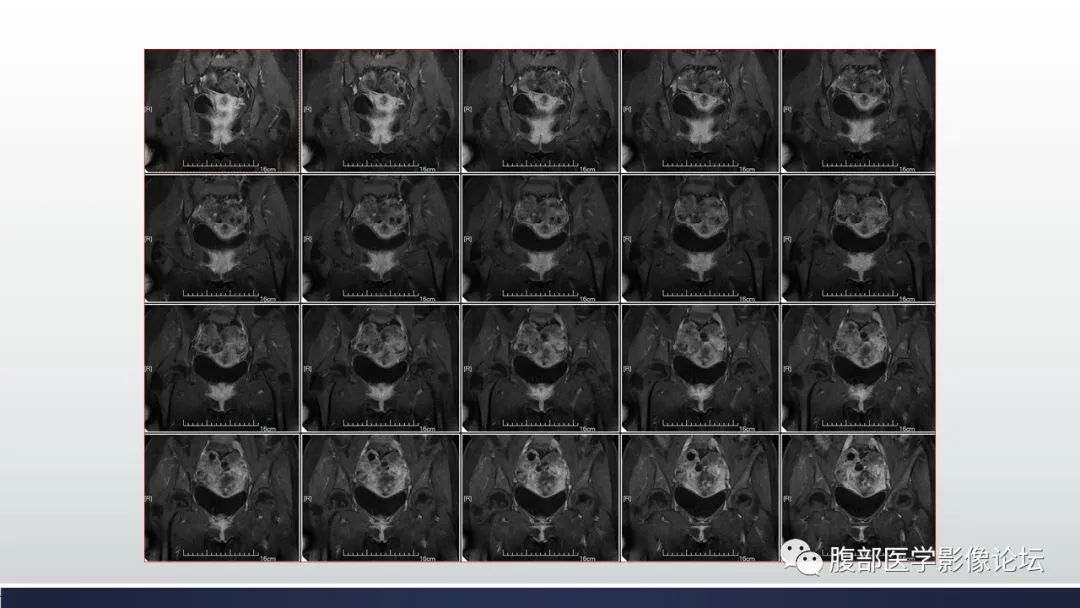

【病例】子宫内膜透明细胞癌1例MR-10

【病例】子宫内膜透明细胞癌1例MR-11

【病例】子宫内膜透明细胞癌1例MR-12

【病例】子宫内膜透明细胞癌1例MR-13

【病例】子宫内膜透明细胞癌1例MR-14